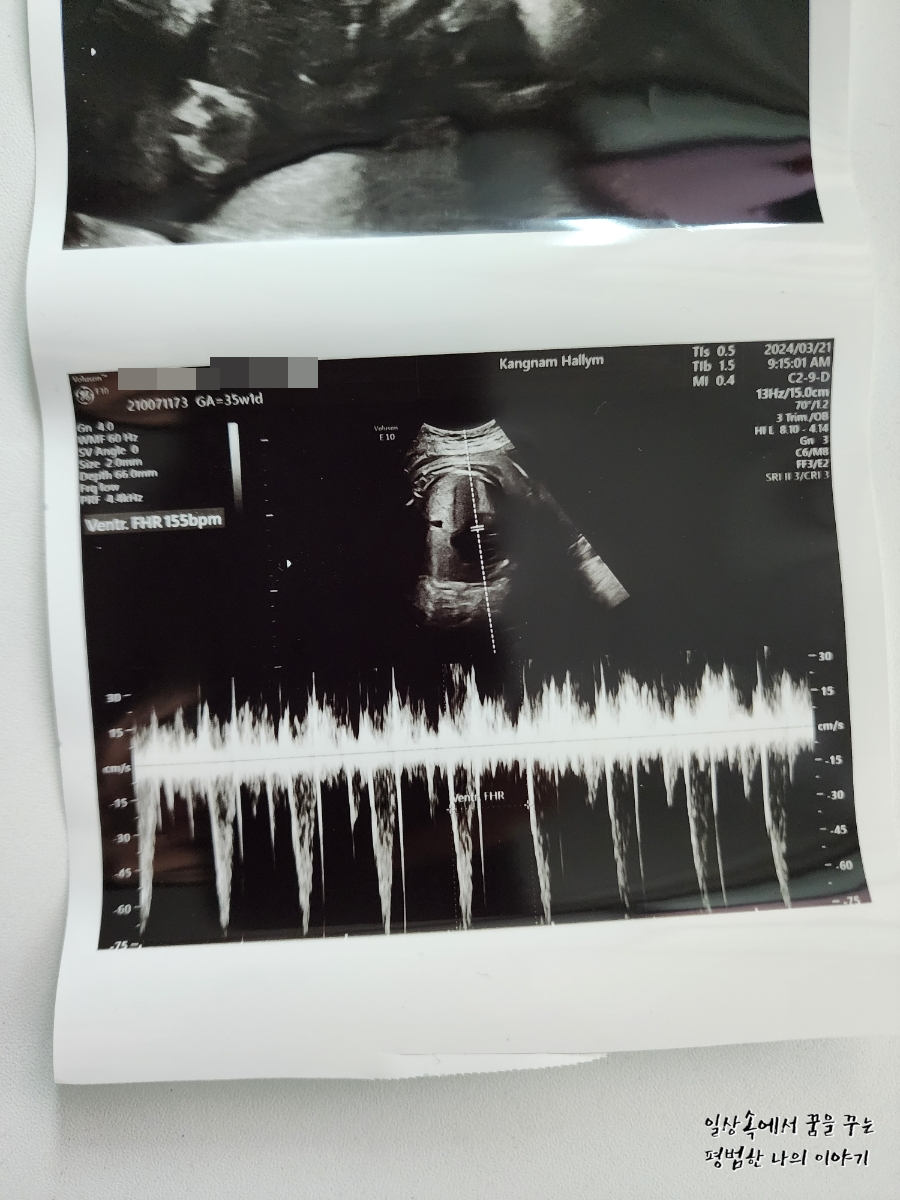

2024년 3월 21일(목요일)

GA(Gestational Age, 임신 주차): 35주 차 1일

FHR(Fetal Heart Rate, 심장박동 수): 155bpm

BPD(Biparietal Diameter, 위에서 볼 때 태아 머리 단면의 가장 긴 길이): 9.05cm

HC(Head Circumference, 태아 머리둘레): 32.55cm

AC(Abdominal Circumference, 배 둘레): 35.06cm

FL(Femur Length, 허벅지뼈 길이): 6.7cm

EFW(Estimated Fatal Weight, 태아 예상 체중)=EBW(Estimated Body Weight): 3251g